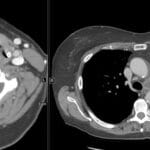

62 yr male presenting with chronic vague abdominal pain, weight loss, and a palpable right-sided abdominal fullness.

Diagnosis: Mesenteric panniculitis with developing lymphoma in the right paramidline mesentery

- The fat halo sign and tumoral pseudocapsule are hallmark CT findings of mesenteric panniculitis that help differentiate it from infiltrative processes like lymphoma.

- Evolution into lymphoma should be suspected if follow-up imaging demonstrates lymph nodes larger than 12 mm, loss of the fat halo sign, or coalescence of nodes into a solid mass.

- CT: Misty mesentery appearance with increased fat attenuation (-50 to -90 HU); well-defined mass often in the left paramidline; presence of small lymph nodes (<10 mm); development of lymphoma suggested by nodes >12 mm, nodal coalescence, and necrosis.

- Signs: Fat halo sign (preserved normal fat density around vessels/nodes); Tumoral pseudocapsule (peripheral soft-tissue band of fibrosis); Misty mesentery (hazy increased fat attenuation).